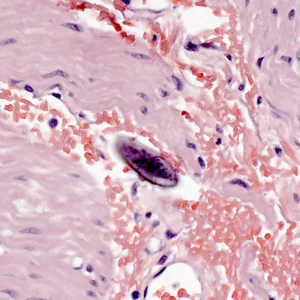

Enterobiasis is frequently asymptomatic. The most typical symptom is perianal pruritus, especially at night, which may lead to excoriations and bacterial superinfection. Occasionally, invasion of the female genital tract with vulvovaginitis and pelvic or peritoneal granulomas can occur. Other symptoms include, teeth grinding, enuresia, insomnia, anorexia, irritability, and abdominal pain, which can mimic appendicitis. E. vermicularis larvae are often found within the appendix on appendectomy, but the role of this nematode in appendicitis remains controversial. Very rare instances of eosinophilic colitis associated with E. vermicularis larvae have been reported.